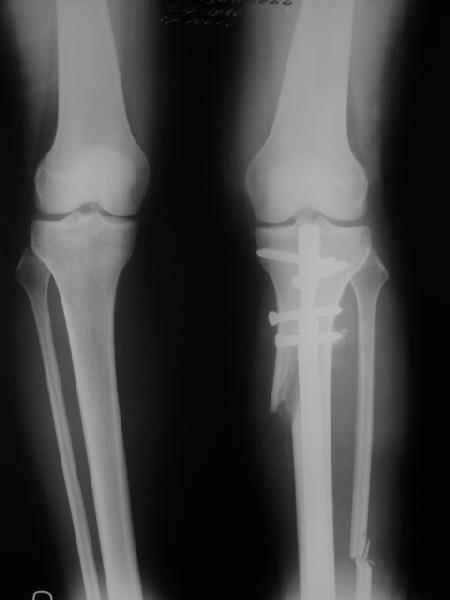

Как уже писал, вчера сделал одну ногу (может, свой плюс будет что не обе- вдвое меньше травма, сразу на костыли встанет, оперированную ножку немного разомнет, тут и вторую заделаем).

Снимки в приложении - фас сравнительный с неоперированной ногой. Жду критики.

Впрос про остеотомию большеберцовой непраздный. Эта получилась при надломе несколько более наклонно, чем я делал (сейчас проблема,

как на второй ноге сделать так же). Вот этот высоящий "зуб" центрального отломка не заменит ли в плане косметики то, что получается при медиализации дистального?